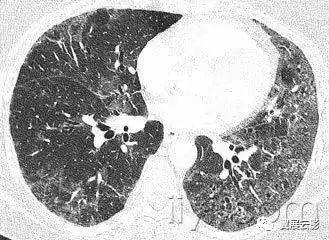

二十、铺路石征:

CT扫描:铺路石征表现为磨玻璃影背景上小叶间隔和小叶内线增厚,呈现不规则的铺路石征。铺路石征常与相对正常肺组织分界清楚,边缘规则。该征象最早报道于肺泡蛋白沉积症,也可见于其他类型同时累及肺间质和肺实质的弥漫性肺疾病,包括脂性肺炎。